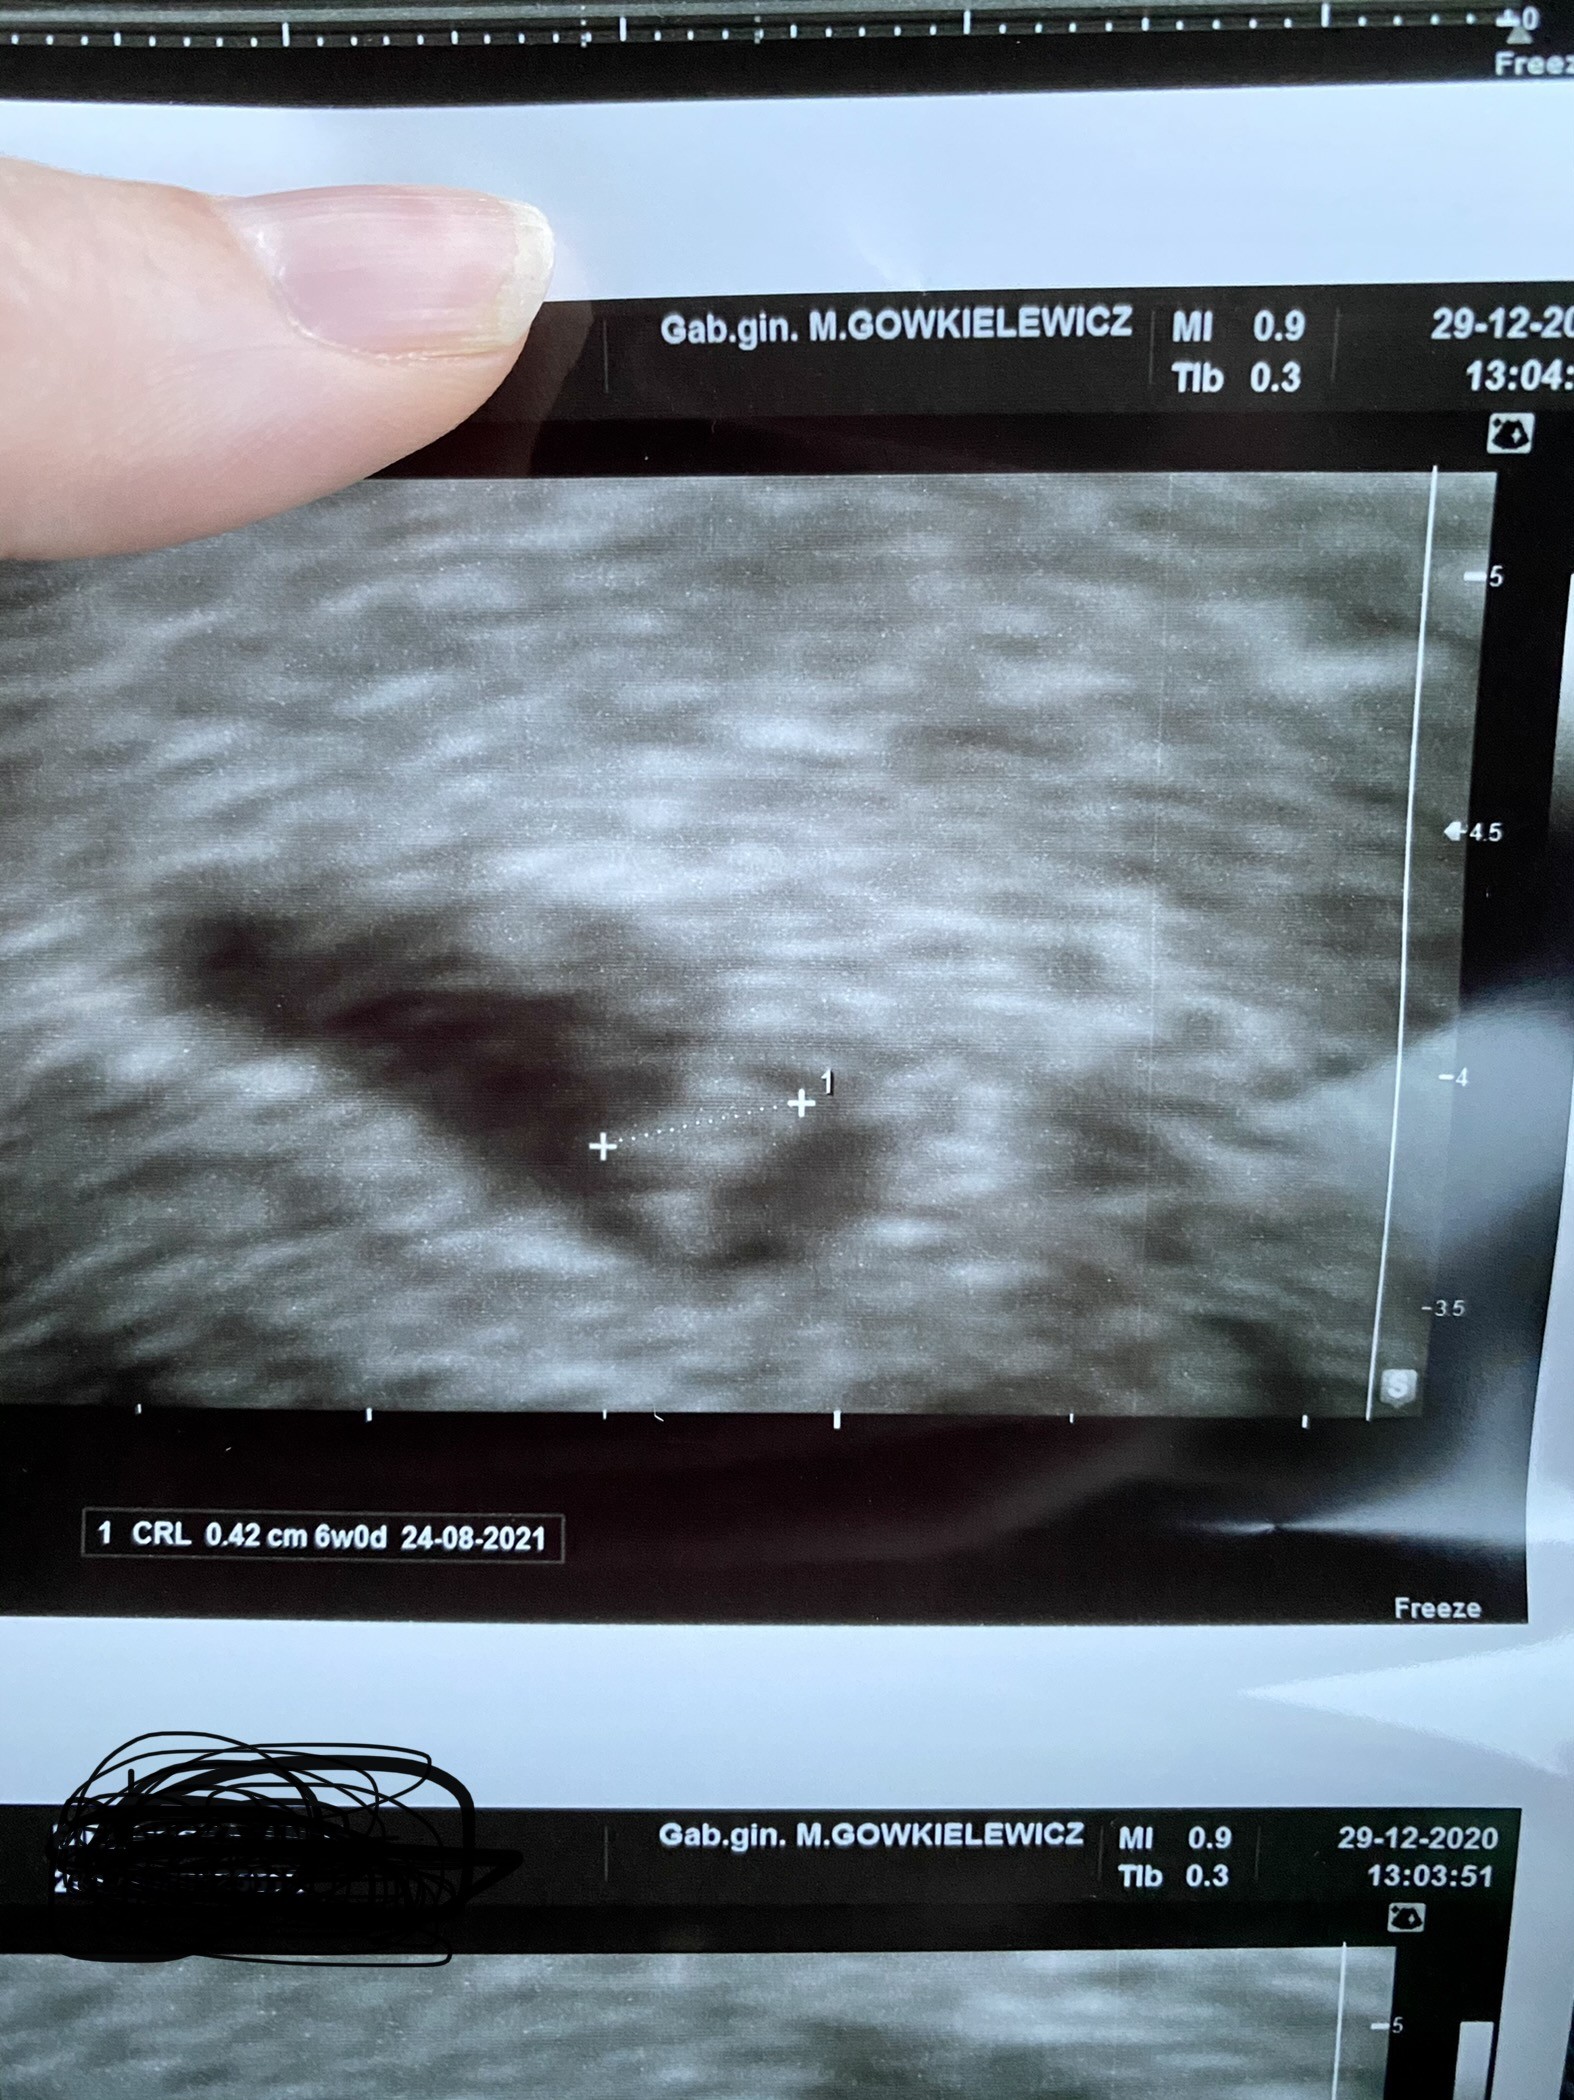

Dziewczyny powiedzcie mi czy któraś z Was wstawiała zdjęcie z usg z 6-7 tygodnia na grupę ramzi zagraniczna lub polska? I czy się sprawdziło to co dziewczyny napisały odnośnie płci [emoji846]

Juz ci pokazuje zdjecie. Usg bylo dopochwowe. Wrzucalam na angielska strone.

Ja wstawiałam i mi się nie sprawdziło, ale dziewczyny nie zwracają uwagi na typ usg - dopochwowe czy przez brzuch. A wg tego co wyczytałam w necie to u mnie ramzi się sprawdził bo Usg dopochwowe = lustrzany obraz, czyli było dziewczynkowo. I będzie córka. Porownalam z chłopakami i faktycznie z nimi było na odwrot. Wrzuciłam na stronkę i powiedziały ze z ramzi dziewczynka a to było usg moich chłopcówDziewczyny powiedzcie mi czy któraś z Was wstawiała zdjęcie z usg z 6-7 tygodnia na grupę ramzi zagraniczna lub polska? I czy się sprawdziło to co dziewczyny napisały odnośnie płci![]()

Zobacz załącznik 1255384

A mogłabyś dodać zdjęcia? U mnie jak patrzyłam teraz na obraz usg podczas badania zarodek był cały czas po lewej stronie macicy a na zdjęciu które lekarz wydrukował jest po prawej czyli właśnie lustrzany obrazJa wstawiałam i mi się nie sprawdziło, ale dziewczyny nie zwracają uwagi na typ usg - dopochwowe czy przez brzuch. A wg tego co wyczytałam w necie to u mnie ramzi się sprawdził bo Usg dopochwowe = lustrzany obraz, czyli było dziewczynkowo. I będzie córka. Porownalam z chłopakami i faktycznie z nimi było na odwrot. Wrzuciłam na stronkę i powiedziały ze z ramzi dziewczynka a to było usg moich chłopcówwiec totalnie na odwrot Haha!